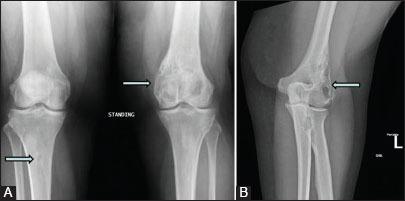

Sinus histiocytosis with massive lymphadenopathy (SHML) or Rosai-Dorfman disease is a non-neoplastic condition which typically presents as massive, bilateral cervical lymphadenopathy and can involve multiple extranodal organ systems such as skin, eyes, and upper respiratory tract in about 28% cases. Bone lesions in association with nodal disease are seen in less than 10% cases. Isolated bone involvement as the only manifestation of SHML is extremely rare, with less than 50 cases reported in the literature. We report a very uncommon case of Rosai-Dorfman disease with isolated multifocal osseous involvement as the only presenting feature, involving about 10 different sites with no lymphadenopathy or other organ system involvement.

伴巨大淋巴结病的窦性组织细胞增生症(SHML)或罗萨伊-多夫曼病是一种非肿瘤性疾病,通常表现为双侧巨大颈部淋巴结病,约28%的病例可累及多个结外器官系统,如皮肤、眼睛和上呼吸道。与淋巴结疾病相关的骨病变见于不到10%的病例。孤立性骨受累作为SHML的唯一表现极为罕见,文献报道不足50例。我们报告了一例非常罕见的罗萨伊-多夫曼病病例,其唯一的表现为孤立性多灶性骨受累,累及约10个不同部位,无淋巴结病或其他器官系统受累。